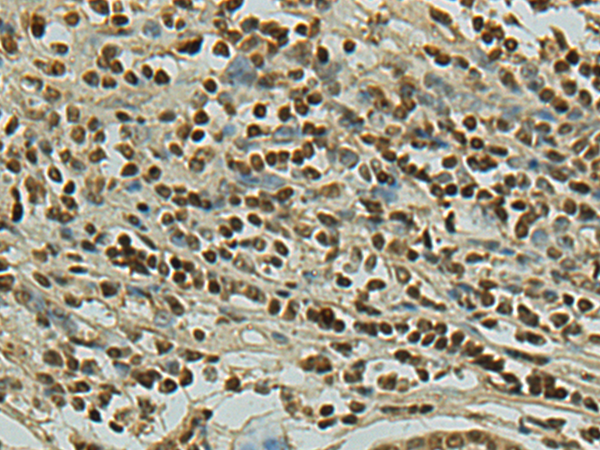

IHC positive control: |

Human gastric cancer |

IHC Recommend dilution: |

100-300 |